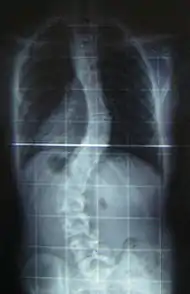

When scoliosis is suspected, weight-bearing, full-spine AP/coronal (front-back view) and lateral/sagittal (side view) X-rays are usually taken to assess the scoliosis curves and the kyphosis and lordosis, as these can also be affected in individuals with scoliosis. Full-length standing spine X-rays are the standard method for evaluating the severity and progression of scoliosis, and whether it is congenital or idiopathic in nature. In growing individuals, serial radio-graphs are obtained at 3- to 12-month intervals to follow curve progression, and, in some instances, MRI investigation is warranted to look at the spinal cord.[81] An average scoliosis patient has been in contact with around 50–300 mGy of radiation due to these radio-graphs during this time period.[82]

The standard method for assessing the curvature quantitatively is measuring the Cobb angle, which is the angle between two lines, drawn perpendicular to the upper end-plate of the uppermost vertebra involved and the lower end-plate of the lowest vertebra involved. For people with two curves, Cobb angles are followed for both curves. In some people, lateral-bending X-rays are obtained to assess the flexibility of the curves or the primary and compensatory curves.